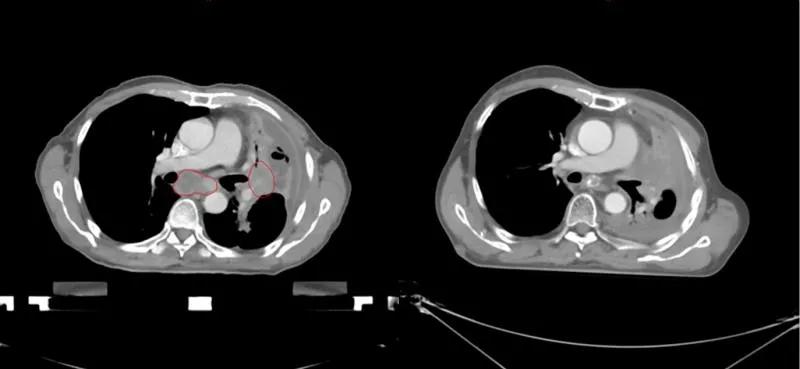

与这些名人患肺癌的同时,笔者治好了至少5位晚期肺癌病人(见下图CT片显示的肿瘤)。笔者病人有咳嗽,咯血,胸痛,胸闷,气急等症状,病人家属知道亲人是晚期肺癌,没有抱多大希望,治疗的目的只是想减轻一些症状,延长生命。经过笔者的精心治疗,2例现已活了5年多,2例已活过3年多,1例已活过2年多。治疗时年龄最大有82岁,最小年龄51岁,他们现在都生活得很好,甚至一个来自江西农村的病人一直在田地里干重体力农活。

治疗前后CT对比,红色为肿瘤(左),治疗后肿瘤消失(右)